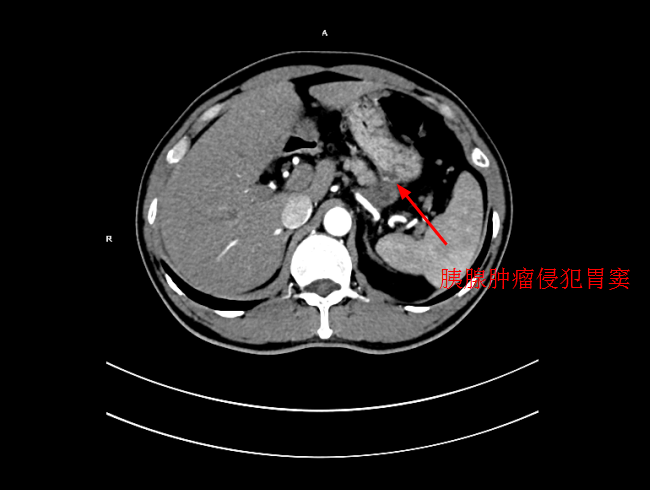

經過檢查後,确診爲局部晚期胰腺癌,大小爲5*3cm,癌細胞已侵犯胃窦。考慮到傳統化療方式,藥物經身體多重代謝後,到達胰腺的濃度低,達不到很好殺滅腫瘤組織的效果,且對正常組織具有一定的毒副作用。爲此李旭丹主任決定給予采用DSA下介入灌注化療,得到患者及其家屬的支持。